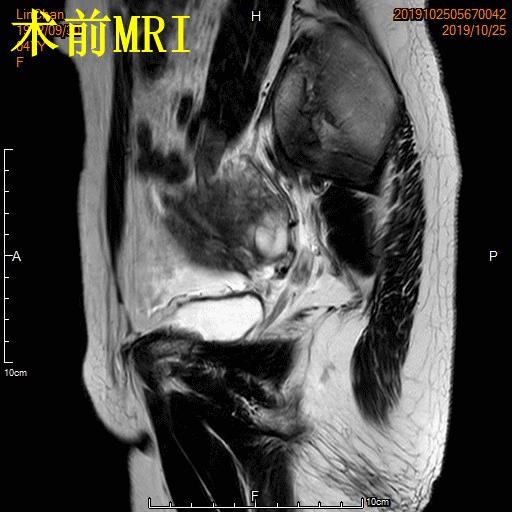

例3

中年患者,发现“子宫腺肌症”10年余,近5年痛经、月经量增多等症状明显加重,导致贫血,严重影响生活质量。MRI检查显示子宫明显增大,子宫前壁明显增厚,合并粘膜下子宫肌瘤。术前诊断为子宫腺肌症合并粘膜下子宫肌瘤。

- 经桡动脉入路UAE,术后患者无需长时间卧床、下肢制动,可明显提升术后舒适度,减少术后并发症,促进术后快速康复!